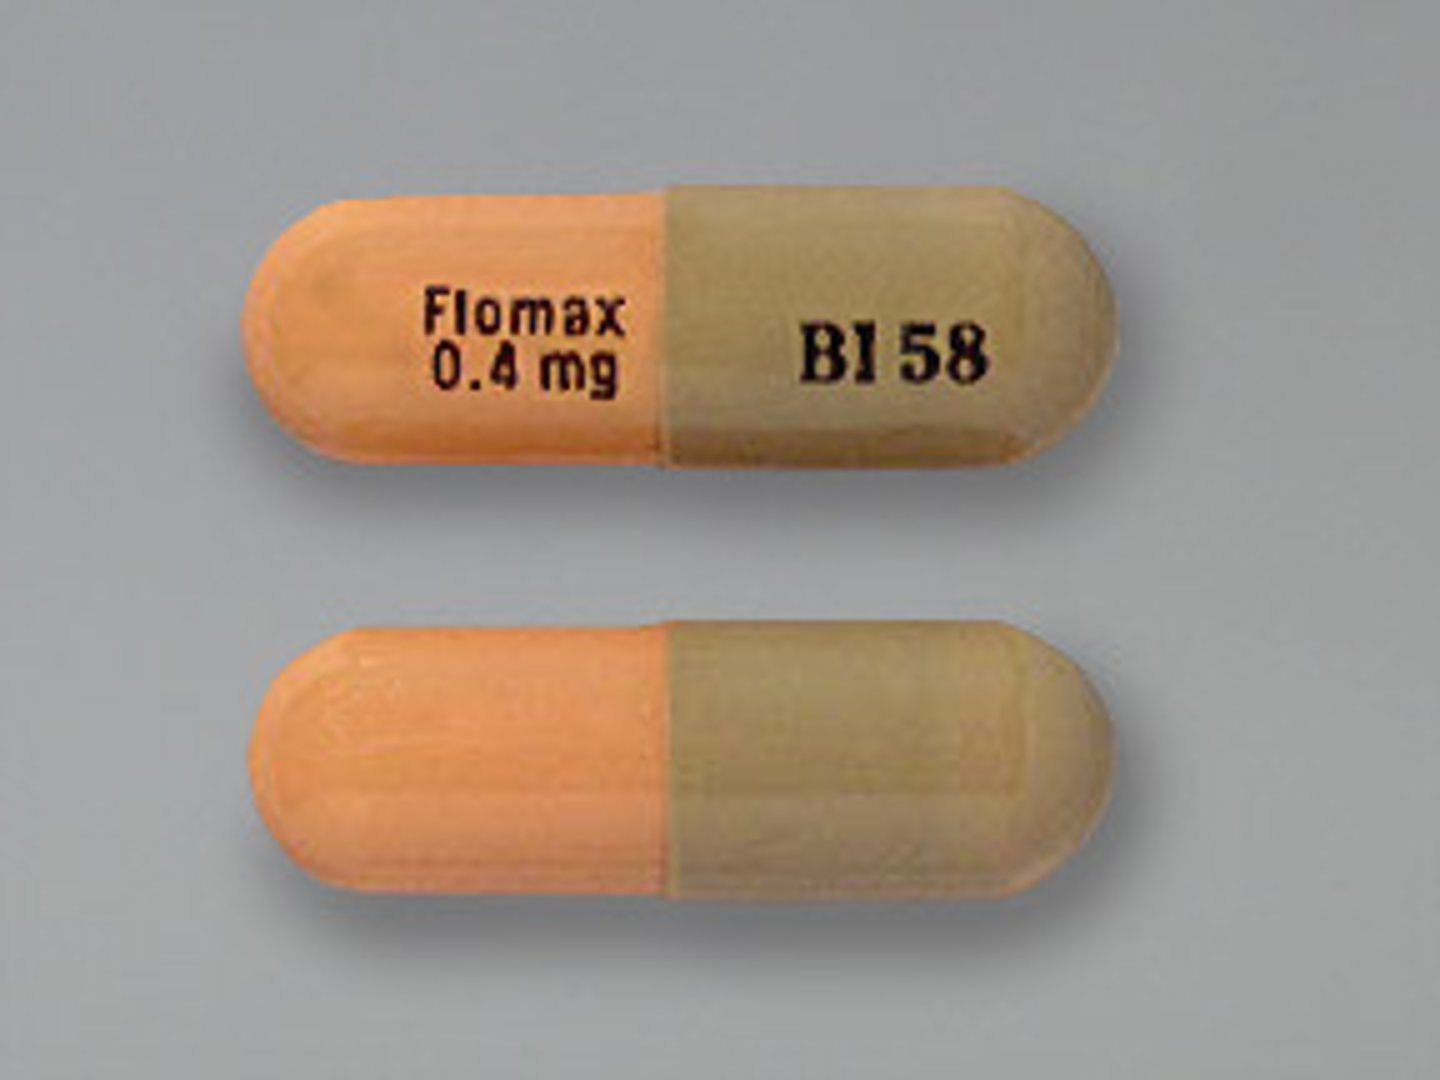

Tamsulosin

Brand: Flomax

Class: Alpha-Blocker

Indication: Enlarged Prostate

Schedule: NCLM